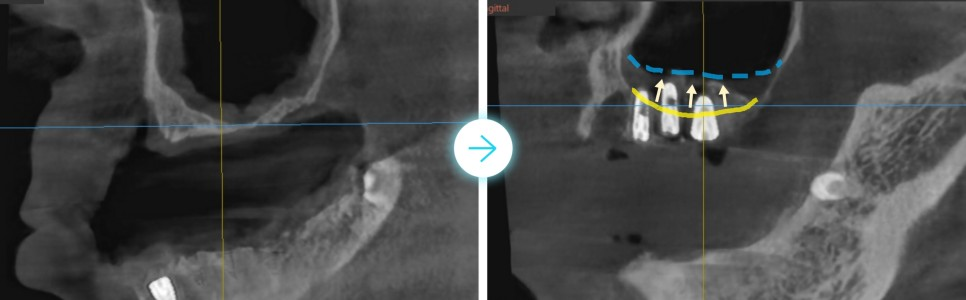

(아래 사진) 3D 파노라마 사진으로 좀 더 상세히 살펴보겠습니다.

원래 파란 점선에 있어야 하는 잇몸뼈 라인이

치아 뿌리 끝에 위치한 노란색 실선 부위까지 내려앉은 것이 보입니다.

이 정도로 잇몸뼈가 내려앉은 경우, 치아가 빠지는 것이 이상하지 않고

그 옆 자연치아들도 치아 뿌리 끄트머리만 간당간당하게 박혀있어

머지않아 빠질 것이 확연해 보입니다.

(아래 사진) 임플란트 주변 염증 상태를 살펴보면,

아래 앞니 임플란트 부위는 다른 부위에 비해 유독 잇몸뼈가 많이 내려간 것이 보입니다.

(노란색 실선이 잇몸뼈 라인)

뿐만 아니라, 위 치아 잇몸뼈도 임플란트 기둥 절반 수준까지 상당 부분 내려간 것이 확인됩니다.

위, 아래 모두 전형적인 임플란트 주위염의 모습입니다.